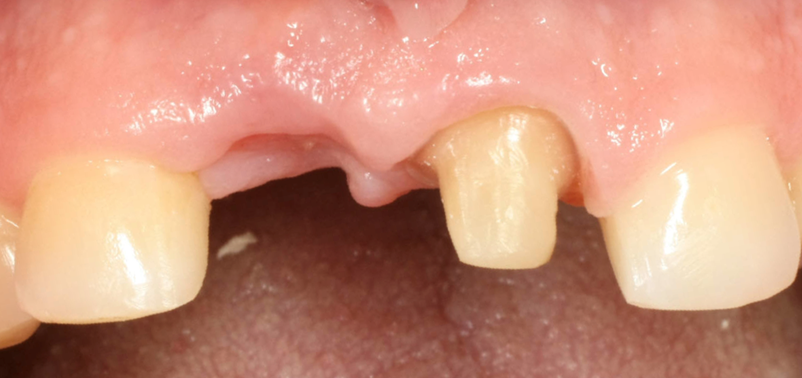

Immagine clinica e radiografica al momento della rimozione della membrana

Inserimento implantare dopo quattro mesi